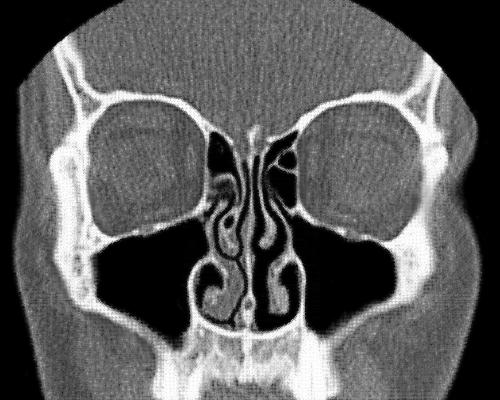

© Wikipedia第一个告诉我人类拥有两个鼻子的论点是由罗纳德·埃克尔斯(Ronald Eccles)提出的,他是威尔士卡迪夫大学(Cardiff University)感冒研究中心的鼻腔专家,直到几年前退休。我知道这听起来很荒谬,但请考虑一下你的鼻子,或者说你的两个鼻子在内部是什么样子:每个鼻孔通向自己的鼻腔,不直接与另一个鼻孔相连接。它们是两个独立的器官,就像你的两只眼睛或两只耳朵一样。

鼻子远非被动的通道,它隐藏着不断变化的内部结构。正如埃克尔斯所说,鼻子内部有静脉勃起组织,其结构“与阴茎的勃起组织相似”,并且会充血。感染或过敏会加剧肿胀,以至于鼻腔会完全堵塞。

在健康的鼻子中,鼻腔组织的肿胀和消肿通常遵循一个称为“鼻周期”(Nasal cycle)的可预测模式。每隔几个小时,一侧的鼻子会部分充血,而另一侧会打开。随后它们交替进行,来回来回。

正常情况下,人们并不会注意到一个鼻孔总是比另外一个呼吸更费力;人们常在感冒时,即在鼻子比平时更堵的时候,才会注意到这种现象。© Wikipedia威斯康星医学院(the Medical College of Wisconsin)生物医学工程师吉尔赫尔梅·加西亚(Guilherme Garcia)说:“当我告诉人们鼻周期时,大多数人根本不知道这一点。”